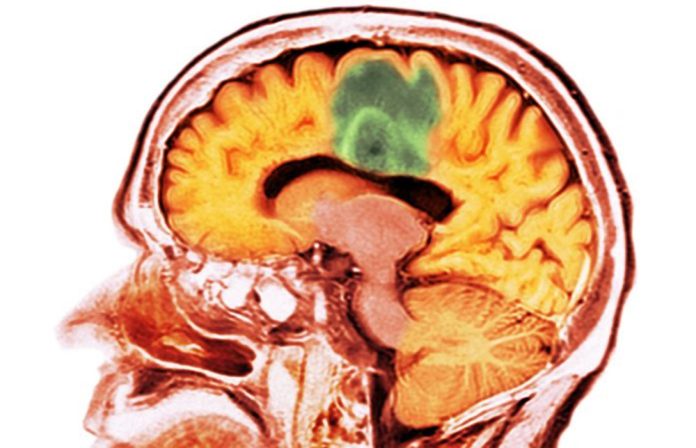

Astrocytomul de grad înalt este o formă agresivă de cancer cerebral cu rate înalte de recurență și rezultate slabe, majoritatea pacienților supraviețuind doar aproximativ patru până la cinci luni după diagnostic. Până în prezent, niciun tratament dincolo de chirurgia standard, radioterapia și chimioterapia nu a reușit să prelungească semnificativ supraviețuirea în această situație.

Deși inhibitorii de puncte de control imunitar au îmbunătățit semnificativ supraviețuirea într-o gamă largă de tipuri de cancer, aceștia au arătat o eficacitate minimă împotriva tumorilor cerebrale. Un motiv principal pentru aceasta este bariera hemato-encefalică, care blochează atât eliberarea antigenelor tumorale în sânge, cât și intrarea celulelor imune în creier pentru a infiltra tumora.

LITT este o procedură minim invazivă care distruge țesuturile tumorale folosind căldura generată de razele laser, ghidate în locația țintă prin imagistică prin rezonanță magnetică (IRM) pentru a asigura că țesutul sănătos nu este afectat. Studii anterioare au arătat că LITT poate face temporar bariera hemato-encefalică mai permeabilă pentru aproximativ patru săptămâni, făcând-o un candidat promițător pentru îmbunătățirea efectelor medicamentelor inhibitorii de puncte de control imunitar în indicațiile de cancer cerebral.